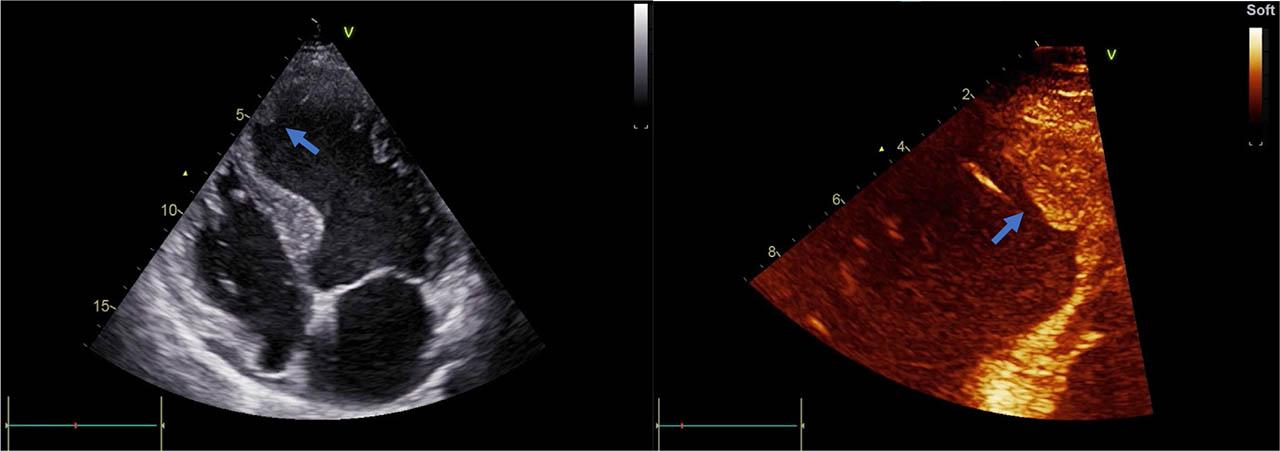

Figure 1